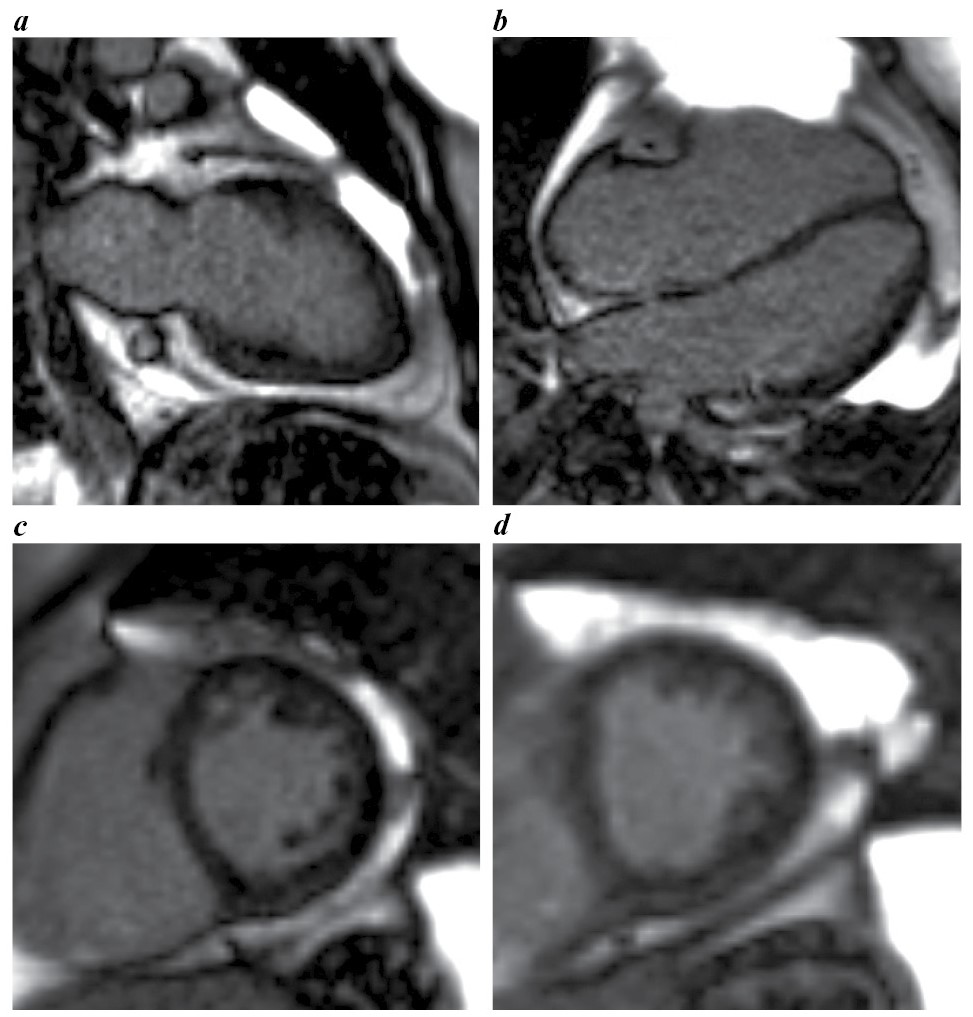

Выполнена магнитно-резонансная томография (МРТ) сердца с контрастированием (рис. 3, a–d), по данным которой очагового поражения миокарда желудочков воспалительного или ишемического характера, признаков отека миокарда и зон фиброза не выявлено. Не обнаружено расширения полостей ЛЖ и ПЖ (индексированный конечный диастолический объем ЛЖ – 60,4 мл/м2, индексированный конечный диастолический объем ПЖ – 47,9 мл/м2). Сократимость ПЖ оставалась в пределах нормы, ЛЖ незначительно снижена – до 54%. Толщина миокарда ЛЖ и ПЖ – в пределах нормы. Визуализировалась трабекулярность боковой стенки ЛЖ, не достигающая критериев некомпактного миокарда (рис. 4, a–d). В полости перикарда не выявлено жидкости, однако обращали внимание скопление эпикардиальной жировой ткани (более 200 г) на уровне атриовентрикулярных борозд, вдоль обоих желудочков, толщиной до 2,3–2,4 см (рис. 5, a–d), также липоматоз межпредсердной перегородки (рис. 5, b), скопление жировой ткани паракардиально (более 100 г).

Рис. 3. МРТ сердца, кино-МРТ, фаза конечной диастолы: a – 2-камерная длинная ось ЛЖ; b – 4-камерная длинная ось ЛЖ; c, d – короткая ось ЛЖ через базальный и средний сегменты.

Fig. 3. Cardiac MRI, cine-MRI, end-diastole phase: a – 2-chamber long axis of the LV; b – 4-chamber long axis of the LV; c, d – short axis of the LV through the basal and middle segments.